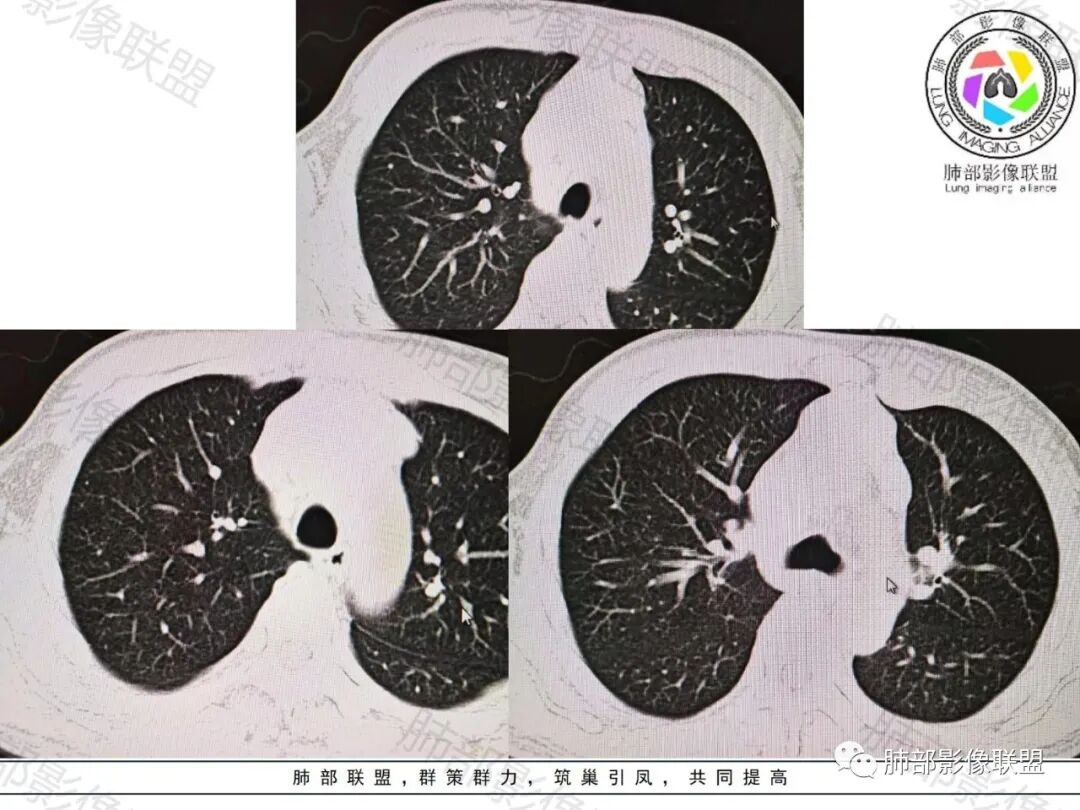

空格: 恶性无异议!抛开纵膈主灶,肺内以两侧斜裂局限弥漫增厚,小结节主要分布在水平裂周围,左下肺纹有串珠状改变,单以肺内分析,淋巴道受累为主。脊柱及肋骨的改变,常见于转移灶,骨淋巴瘤什么样不太熟悉。纵膈内前纵膈为主,腔静脉后也有,位置比较高,形态结节状,部分融合,没有明确的坏死,强化也较均匀,这几点似乎淋巴来源大于胸腺。所以淋巴来源排前面,到底是原发淋巴瘤,多部位侵润,还是猪脚没出场,躲在腹部,胸部都是转移灶?需要腹部检查后决定。患者体重无减轻,主角在腹部的可能性非常小了,主角应该都在台面上了。脊柱的改变,是淋巴瘤的命门。

*肺内见多发结节,呈串珠样分布,淋巴?

*内乳淋巴结增大

*前纵隔病变,淋巴转移?还是都是淋巴结?

*血管包在里面

2.前纵隔不规则块影,密度均匀,有多结节堆积融合感,边界隐约可辨,轻度不均匀强化。3.块影包埋并挤压左无名静脉。相邻大血管均未见侵犯,纵隔两侧胸膜未见突破,未见胸腔积液,右侧叶裂结节样增厚。

4.左内乳淋巴结肿大,上纵隔及右颈根部淋巴结肿大。

1.胸腺所在地不规则块影,有多结节堆积融合感,淋巴结肿大,胸椎骨及肋骨破坏,恶性肿瘤判断当无异议。

多结节堆积融合感,内乳淋巴结等肿大,似乎提示我们更像是淋巴瘤,淋巴瘤界外浸润骨骼并不少见。